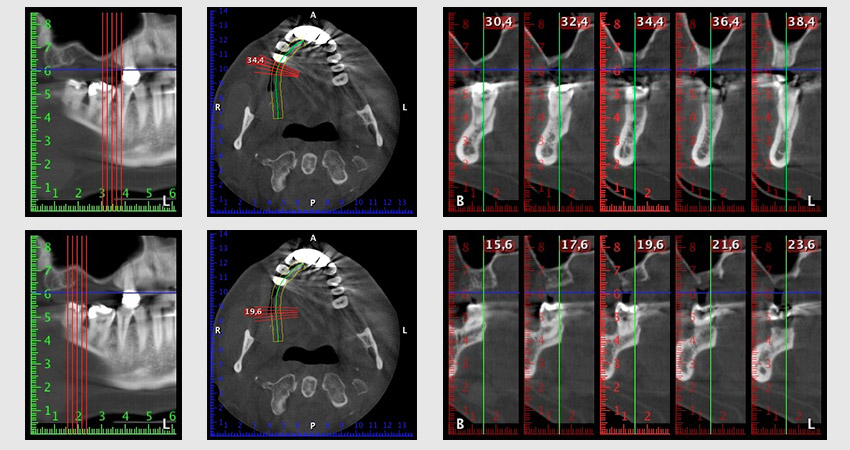

The 59-year-old patient presented with an advanced case of periodontitis, describing an unpleasant feeling and poor taste from the first quadrant in a distal direction. The clinical examination revealed generally enlarged periodontal pockets and very advanced bone atrophy in regions 16 and 14. The radiology confirmed the findings (Fig. 1). Teeth 16 and 14 could not be retained.

Image 1: Orthopantomogram with bone atrophy in region 16–14. *

About six months after teeth 16 and 14 were extracted, a digital volume tomography (DVT, Planmeca) examination was performed for planning and risk minimization purposes. It clearly showed that the bone had not regenerated to the desired volume (Fig. 2 to 7).